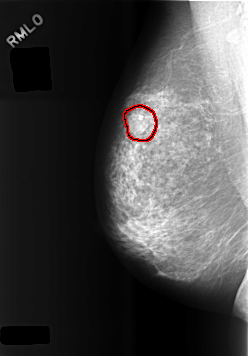

C_0474_1.RIGHT_MLO

RIGHT_MLO LINES 5696 PIXELS_PER_LINE 3960 BITS_PER_PIXEL 12 RESOLUTION 50 OVERLAY

FILE: C_0474_1.RIGHT_MLO.OVERLAY

TOTAL_ABNORMALITIES 1

ABNORMALITY 1

LESION_TYPE MASS SHAPE OVAL MARGINS MICROLOBULATED

ASSESSMENT 4

SUBTLETY 5

PATHOLOGY BENIGN

TOTAL_OUTLINES 1

BOUNDARY